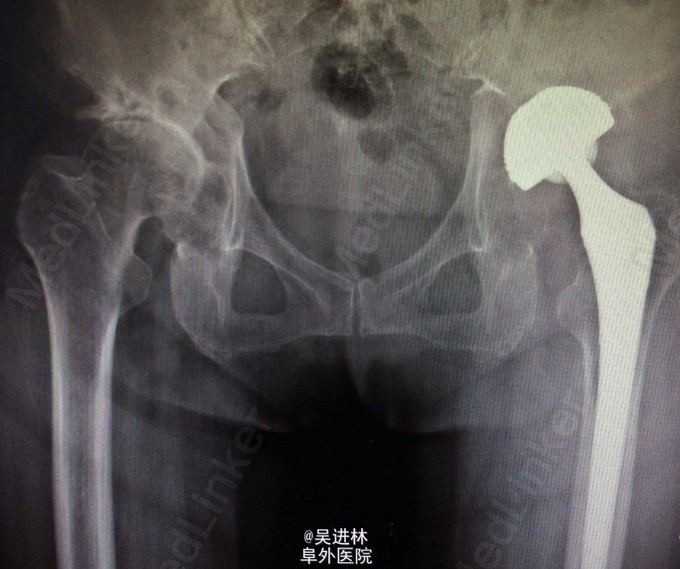

患者老年女性,63岁,主因:左侧全髋关节置换术后一年,疼痛3月入院。患者一年前因股骨头坏死行手术,三月前无明显诱因出现左髋部疼痛,以左大腿明显,呈钝痛,活动后疼痛。 患者查体局部无红肿热,ESR,CRP正常;骨扫描左大腿有浓集灶。今日讨论,有的主任认为是低度感染,有的认为是假体不适造成(如图,该假体旋转中心不在同一水平,型号大),更有主任说德国人遇到这种情况全部当感染来翻修。你怎么看呢?目前怎么处理?